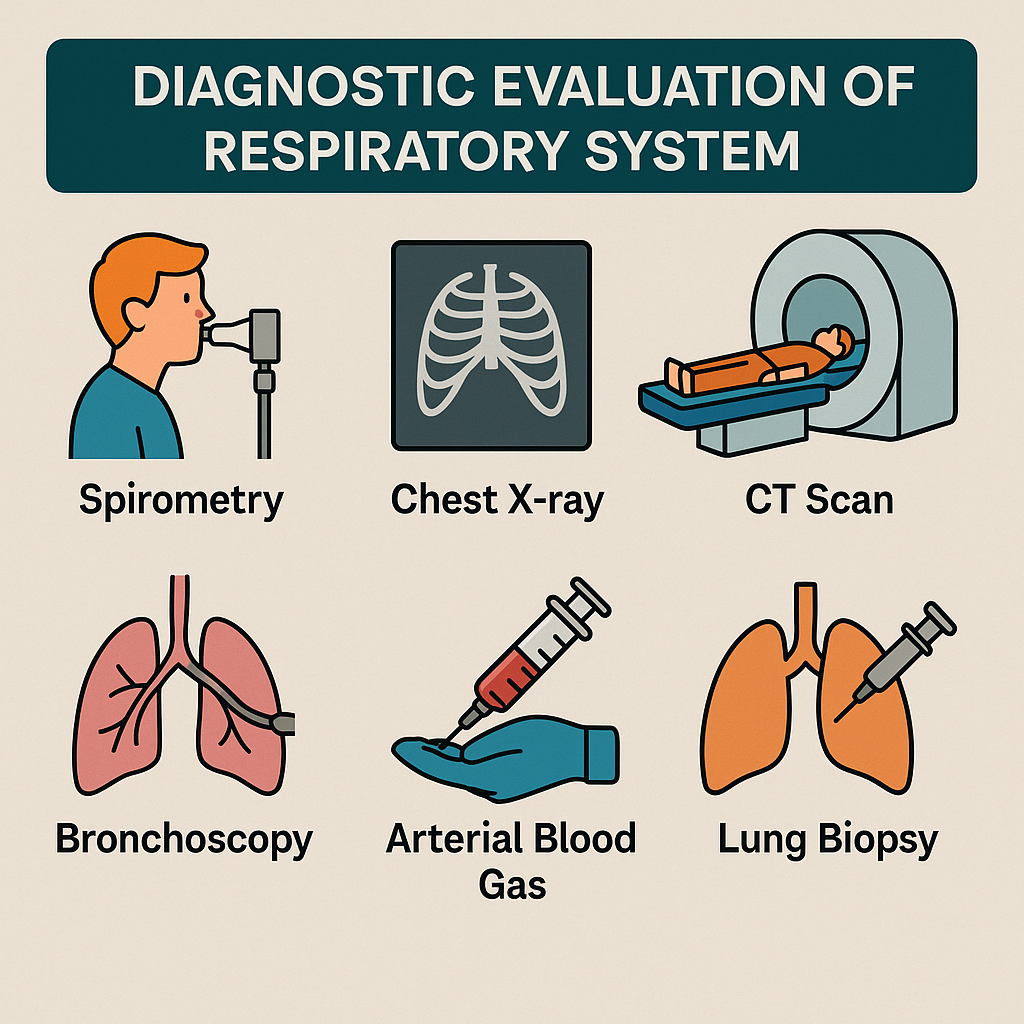

Diagnostic evaluation (ડાયગ્નોસીસ ઇવાલ્યુએશન):

Imaging studies (ઇમેજિંગ સ્ટડીસ):

- જેમાં એક્સરે, સીટી સ્કેન, એમ. આર. આઇ, એન્જિયોગ્રાફી અને વેન્ટિલેશન પરફ્યુઝન લંગ સ્કેનનો સમાવેશ થાય છે.

Chest x-ray (ચેસ્ટ એક્સરે):

CT-scan (સીટી સ્કેન):

Bronchoscopy (બ્રોન્કોસ્કોપી):

Biopsy (બાયોપ્સી):

Lung biopsy (લંગ બાયોપ્સી):